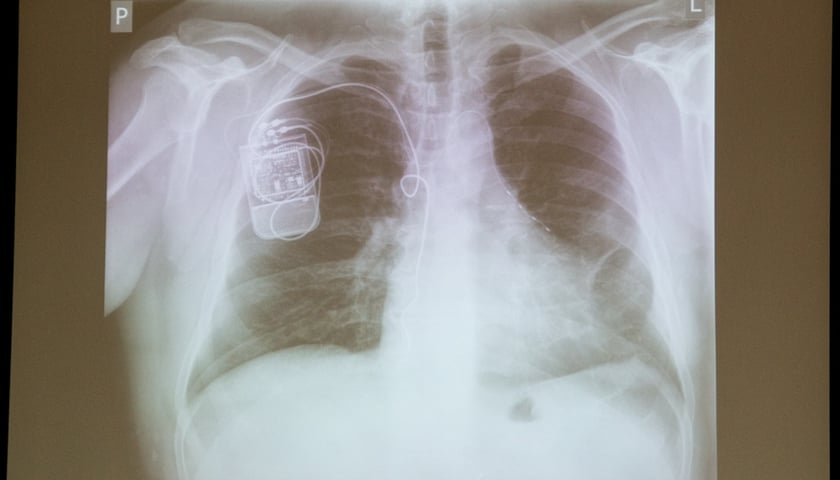

Kardiolodzy z Wojskowego Szpitala Klinicznego we Wrocławiu, jako pierwsi i jedyni w Polsce, pomagają chorym cierpiącym na bezdech senny przy pomocy unikalnej metody. Wszczepiają im w klatce piersiowej specjalny stymulator, który zapobiega bezdechom i zmniejsza liczbę wybudzeń.

Urządzenie, które ratuje pacjentów z bezdechem, to stymulator nerwu przeponowego. Jest wielkości malutkiego telefonu komórkowego.

- Idea zabiegu polega na tym, aby umieścić elektrodę, która będzie stymulować nerw przeponowy – tłumaczy dr n.med. Adam Kołodziej, kardiolog. Zabieg jest małoinwazyjny i odbywa się w znieczuleniu miejscowym. Trwa zwykle kilkadziesiąt minut. Kierownik kliniki podkreśla, że zabieg wymaga dużej biegłości manualnej od lekarza. - Musi on bowiem trafić elektrodą do bardzo cienkiej i fikuśnie biegnącej żyły przeponowej – mówi.

Urządzenie potrafi rozpoznać moment, który poprzedza wystąpienie bezdechu. Wówczas wysyła  impuls do elektrody stymulacyjnej znajdującej się w sąsiedztwie nerwu przeponowego, co zapobiega wystąpieniu bezdechu. Co ciekawe, stymulator działa jedynie w nocy, kiedy chory śpi, i wyłącznie, gdy znajduje się w pozycji leżącej.